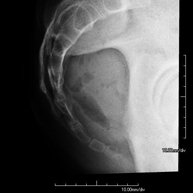

Tècnica que usa els raigs X a través de la qual s'obtenen imatges dels sins paranasals per al seu estudi. Indicacions: dificultat respiratòria nasal, tos crònica, cefalea, mucositat - RX ATM (Articulació Temporo-Mandibular)

Tècnica que usa els raigs X a través de la qual s'obtenen imatges de l'articulació temporo-mandibular per al seu estudi. Indicacions: traumatisme, mal en mastegar, soroll en mastegar, limitació de l'obertura bucal. - RX Càvum